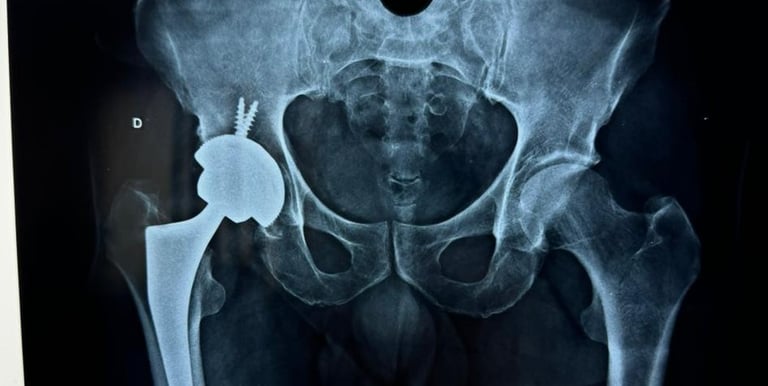

As patologias do quadril podem estar relacionadas a traumatismos prévios,  mas também podem ser secundárias a doenças prévias ou idiopáticas. Algumas das principais patologias  relacionadas ao quadril são: Fraturas da cabeça do fêmur e bacia, Coxartrose, Bursite Trocantérica, Impacto Femoroacetabular, Osteonecrose do Quadril, Síndrome do Piriforme, Tendinite do Quadril.

Tratamento de patologias do Quadril

• Cirurgia de Prótese de Quadril.